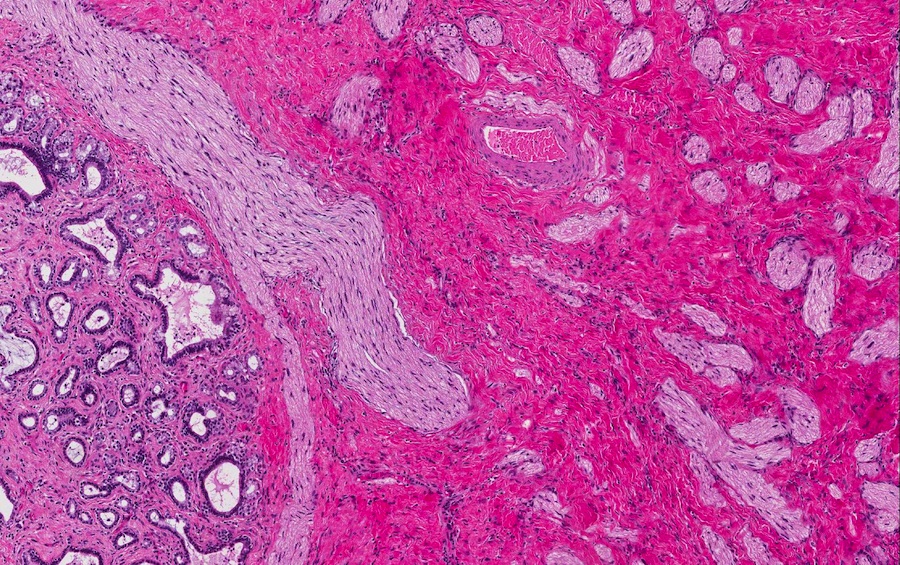

Microscopic images:

Microscopic images:

Both cases showed disorganized and thickened nerve bundles composed of spindle shaped cells, without atypia. Case A also showed a focal foreign body type giant cell reaction adjacent to the disorganized nerve bundles and a strongly immunoreactive S100 stain.

Histology typically shows hyperplastic nerve bundles, positive for S100.

Microscopic images:

Microscopic images:

Both cases showed disorganized and thickened nerve bundles composed of spindle shaped cells, without atypia. Case A also showed a focal foreign body type giant cell reaction adjacent to the disorganized nerve bundles and a strongly immunoreactive S100 stain.

Histology typically shows hyperplastic nerve bundles, positive for S100.